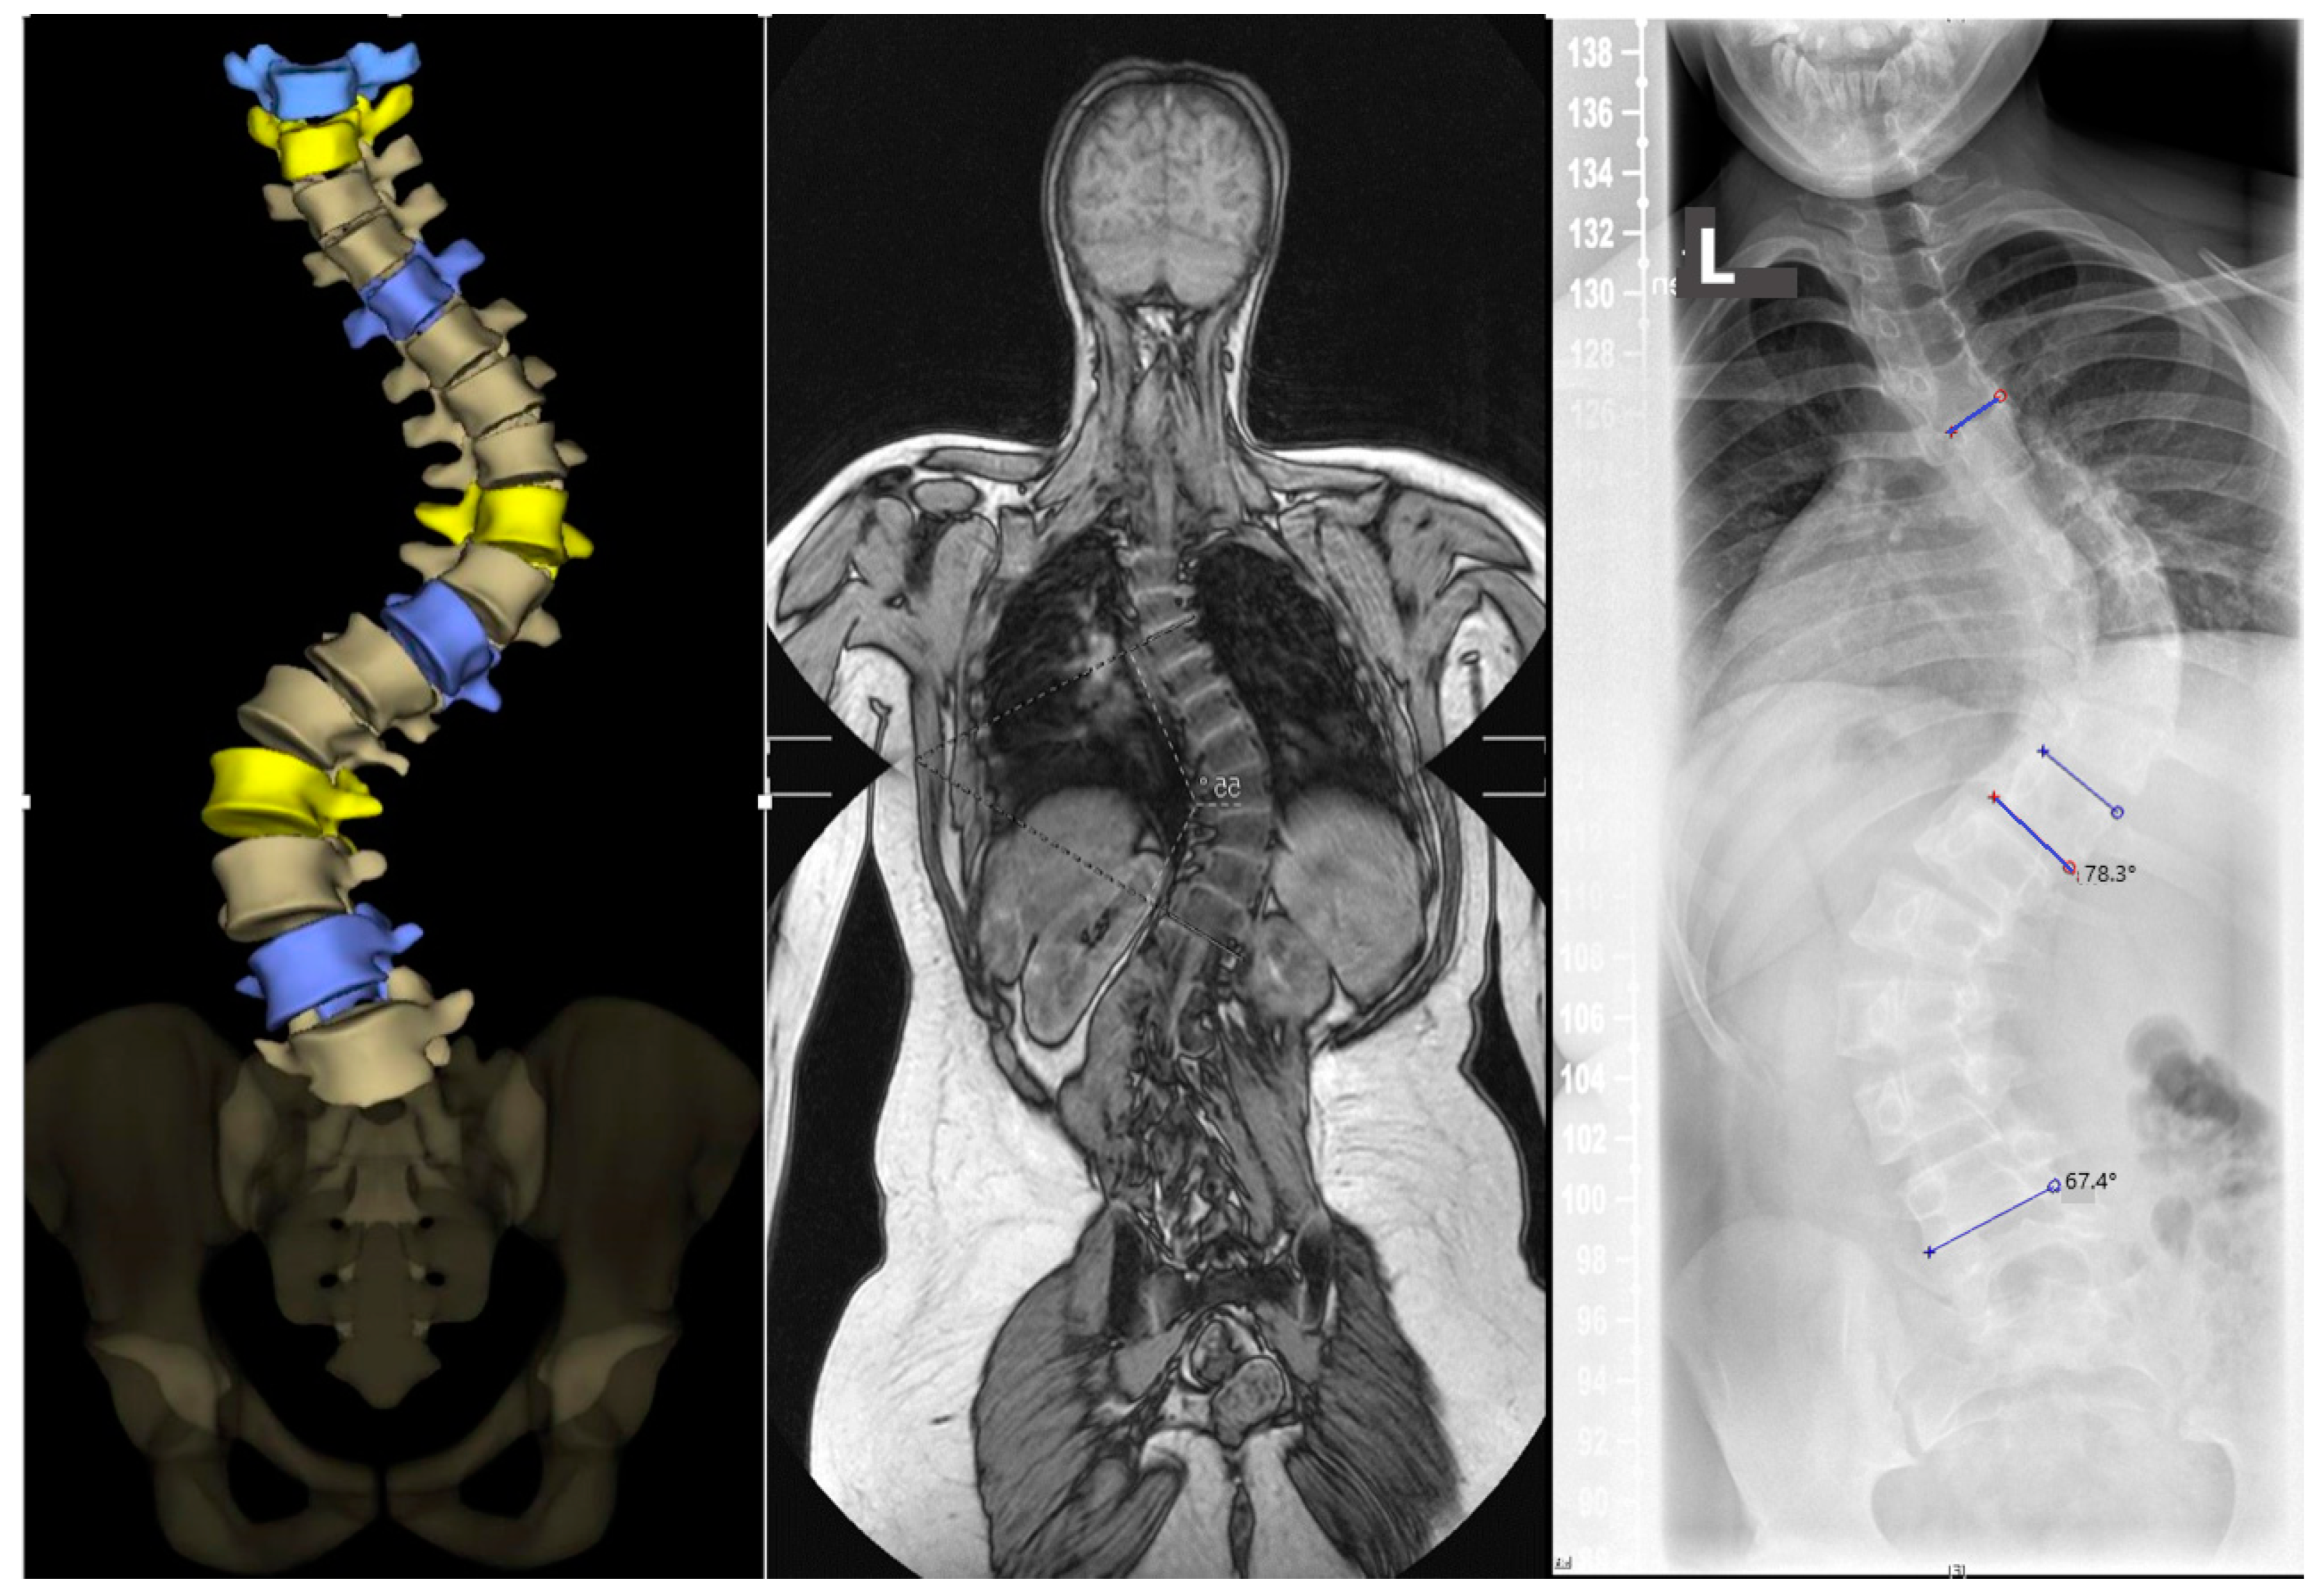

- Can MRI examination with additional thin-slice 3D reconstruction answer all relevant questions for preoperative planning instead of CT? Are EOS or whole spine X-ray examinations in combination with MRI data sufficient for the evaluation of the pedicles and spinal deformity?

- Does the Cobb angle in the radiograph correlate with the calculations from the back scanner image and can follow-up checks be replaced by this video-raster stereography measurement (radiation-free)?

- Cobb angle (thoracic, lumbar).

- Thin-slice 3D MRI examination with reconstruction can answer all relevant questions for preoperative planning instead of CT. EOS or X-ray examination in combination with MRI data is sufficient for imaging pedicles and spinal deformity.

- The Cobb angle in the radiograph correlates with the calculations from the back scanner image, and follow-up checks can be replaced by a three-dimensional back measurement (radiation-free).